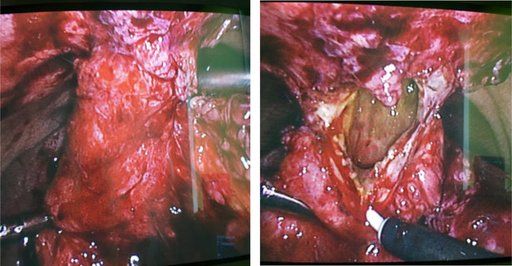

На заключному етапі хірургічного лікування 26.01.2017 р. хворому проведено лапароскопічну холецистектомію